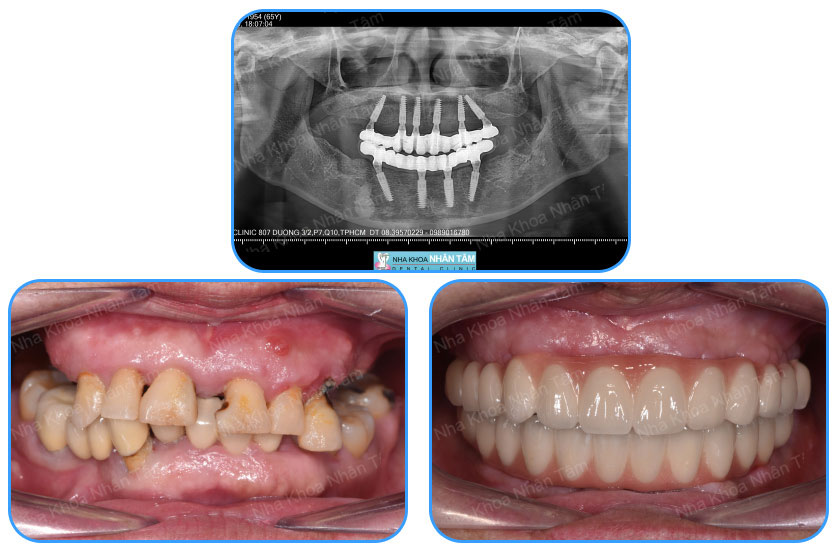

- Mất toàn bộ răng: Các trường hợp mất răng toàn hàm trên hoặc hàm dưới cũng có thể lựa chọn cấy ghép Implant để phục hồi răng mất một cách hoàn hảo. Tùy vào từng trường hợp cụ thể mà có thể lựa chọn cấy ghép Implant đơn lẻ hoặc cấy ghép Implant All on X (All on X là phương pháp cắm từ 2, 3, 4 hoặc 5, 6,... trụ Implant, tùy vào tình trạng của mỗi người. Quá trình cắm trụ sẽ được chia làm nhiều lần, mỗi lần chỉ cắm 2 trụ Implant để đảm bảo an toàn cho khách hàng).

Nha khoa Nhân Tâm là địa chỉ cấy ghép Implant uy tín hàng đầu tại TP.HCM

- Đội ngũ bác sĩ, trợ thủ nha khoa có trình độ chuyên môn cao, giàu kinh nghiệm, đứng đầu là Ts.Bs Võ Văn Nhân – một trong những chuyên gia hàng đầu về cấy ghép Implant tại Việt Nam với hơn 25 năm kinh nghiệm.